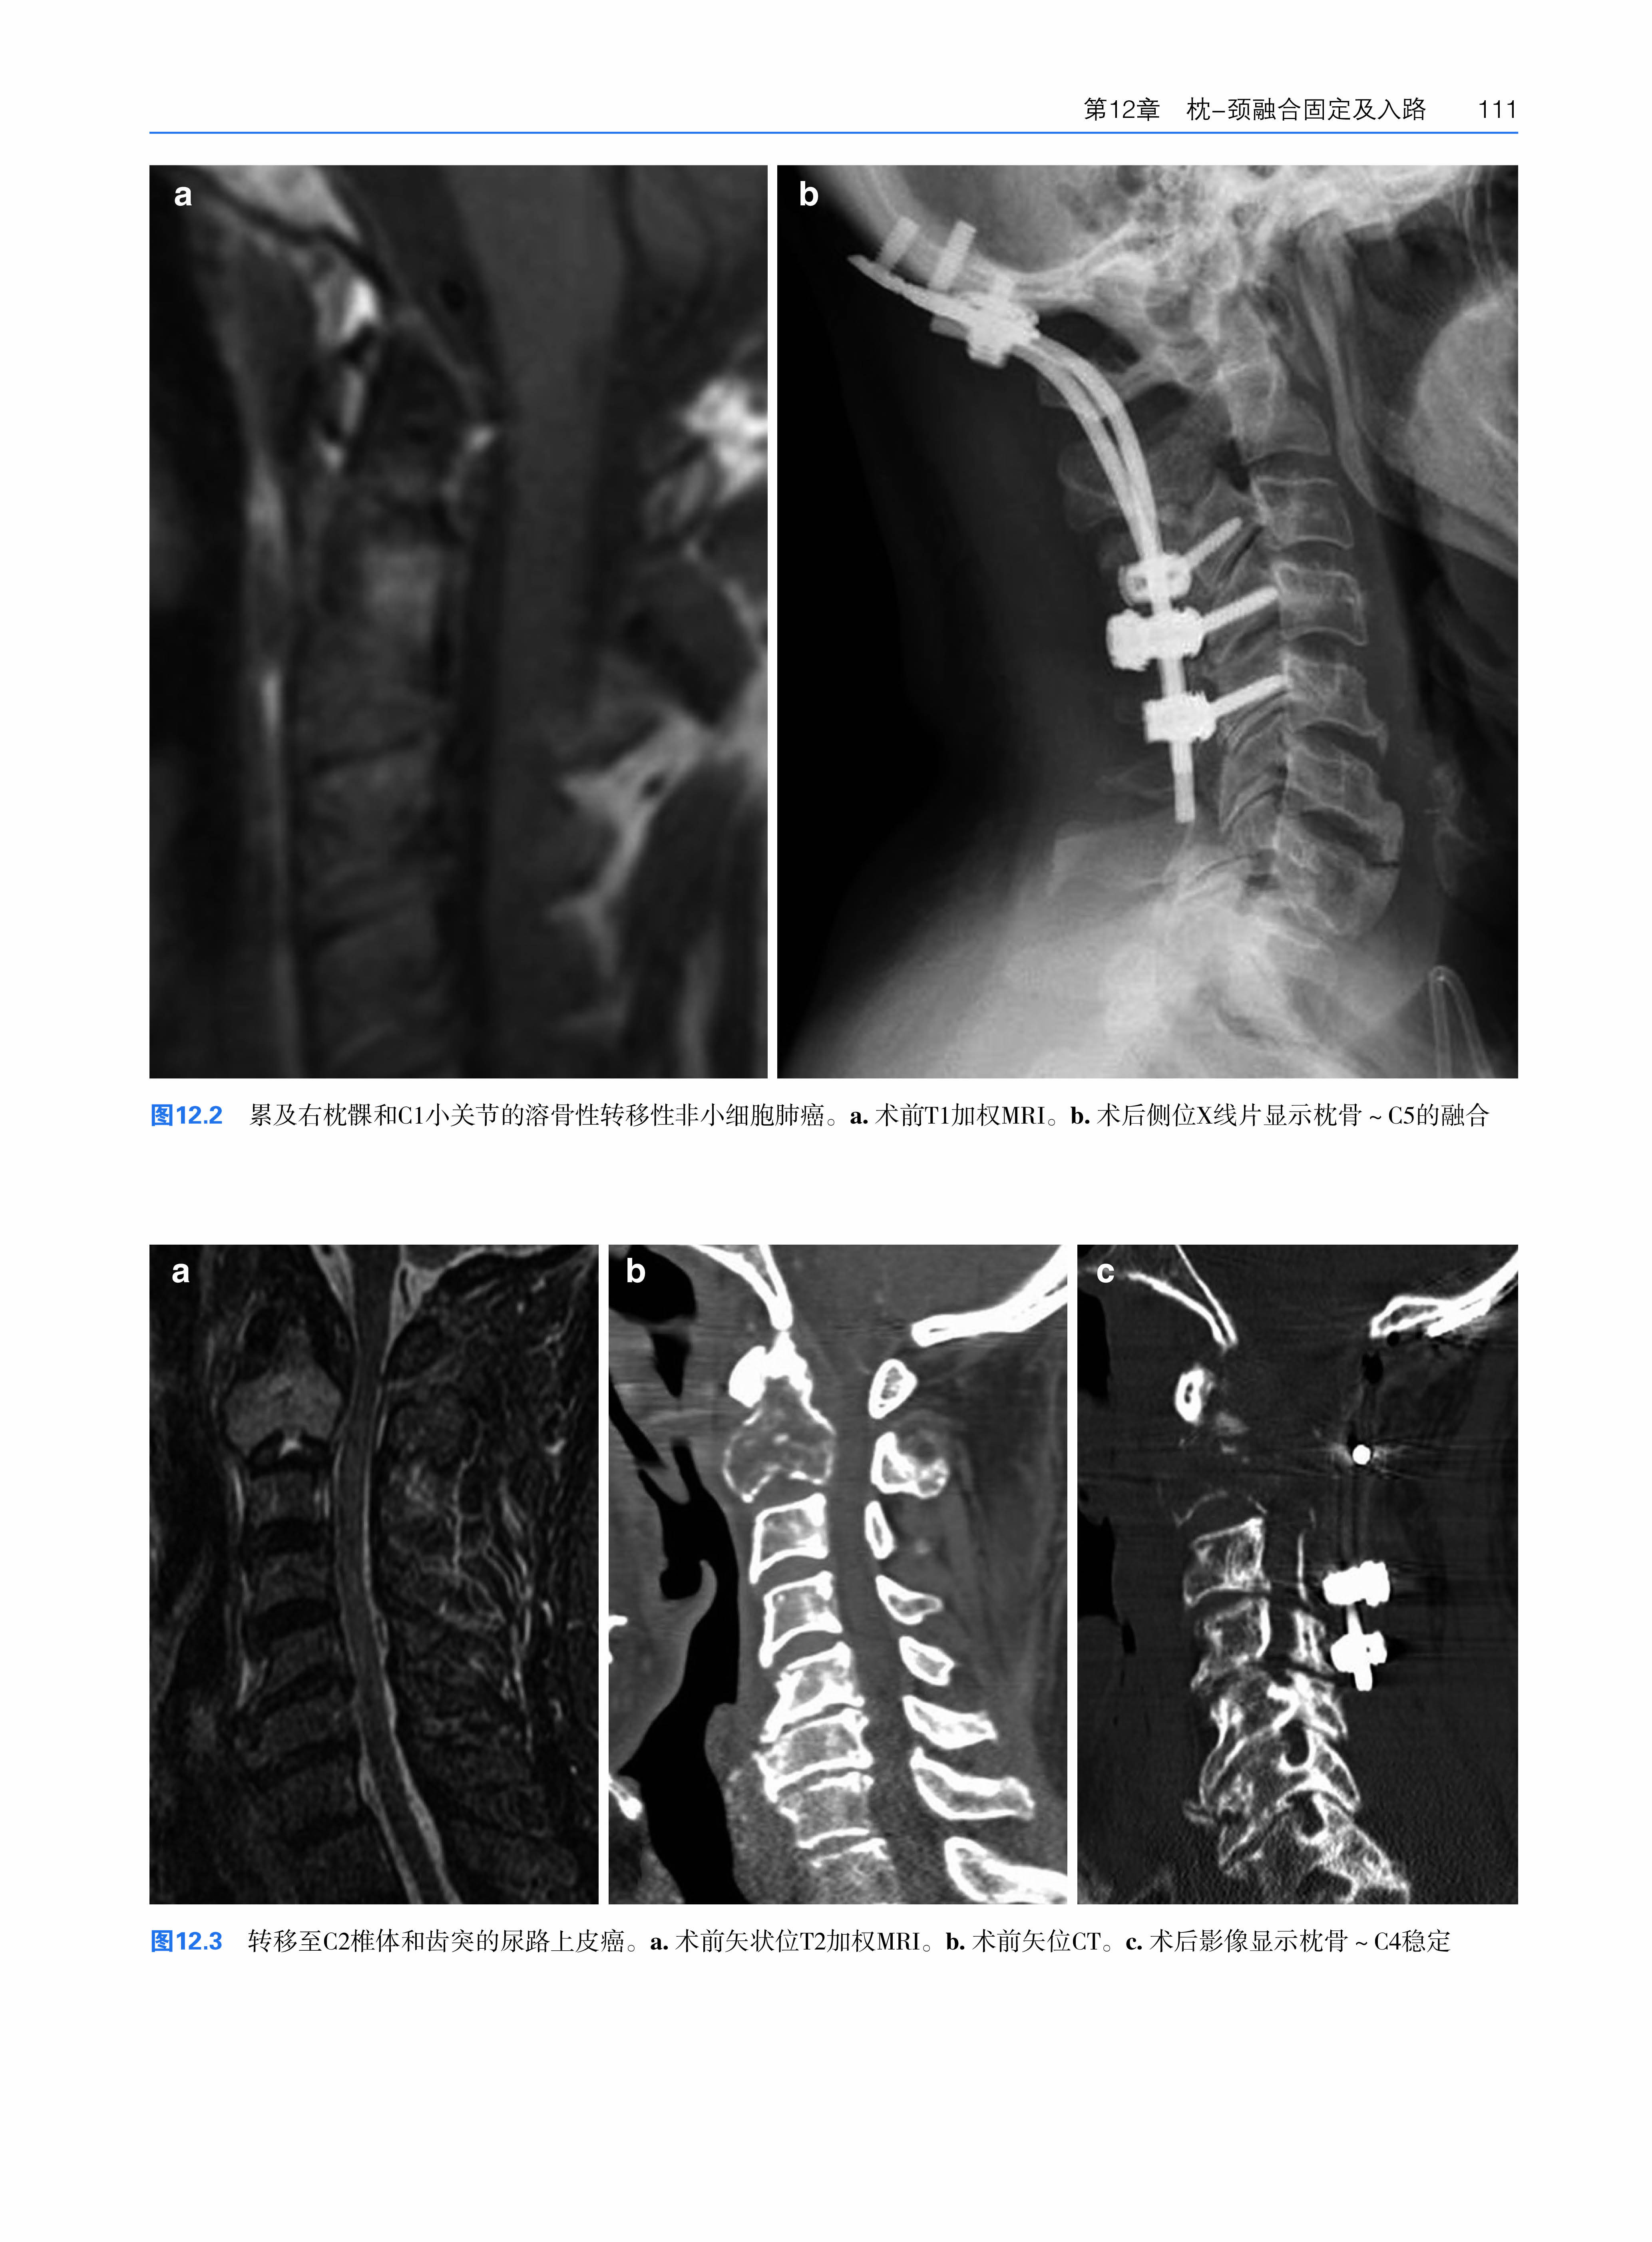

第12章 枕-颈融合固定及入路 ……………………………………………………107

A.Karim Ahmed, Ian Suk, Ali Bydon, Nicholas Theodore